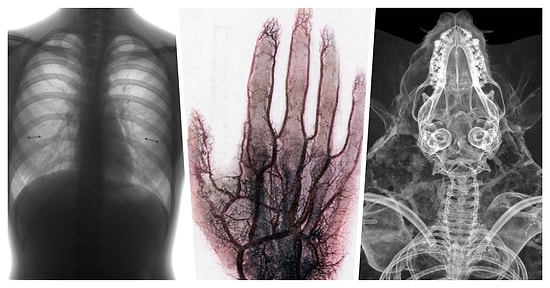

Şişmiş veya mor damarlar hemen hemen herkeste görülebilir ve genellikle tehlikeli olmasalar da bunlara sahip olmak oldukça tatsız olabilir. Her zaman önlenemese de, damarlarımızın şişmesine neden olabilecek günlük olarak yaptığımız bazı eylemler vardır. Damarlarınızı sağlıklı tutmak istiyorsanız hangi günlük alışkanlıklardan kaçınmanız gerektiğini öğrenmek için biraz araştırma yaptık.